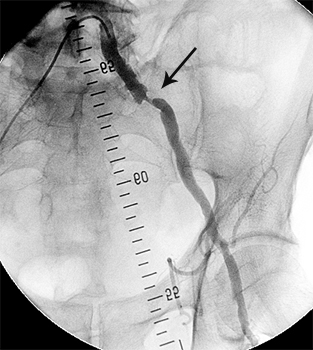

Ангіограми до та після стентування:

стеноз лівої ниркової артерії    балон, роздутий в зоні стенозу    відновлення отвору артерії

Субтотальний стеноз лівої

ниркової артерії